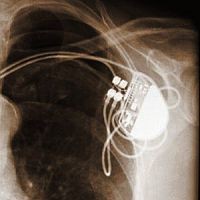

Kifejlesztették az első "MRI-biztos" pacemakerrendszert. Az első "MRI-biztos" pacemakerrendszert engedélyezte az Egyesült Államok gyógyszerügyi hatósága (FDA), az újdonságot a világ legnagyobb orvosi műszergyártó vállalata, az amerikai Medtronic Inc. fejlesztette ki.

A szívritmus-szabályozót alkalmazása a népesség öregedésével egyre gyakoribb, világszerte jelenleg ötmillió beteg visel beültetett pacemakert vagy implantálható cardioverter-defibrillátort (ICD). A pacemakeres betegeknél eddig nem alkalmazhatták az egyik legkorszerűbb diagnosztikai eljárást, az agyi érkatasztrófák (stroke), daganatok, valamint számos neurológiai és ortopédiai betegségek kórismézésére szolgáló mágneses magrezonancia képalkotást, az MRI rádiófrekvenciája ugyanis zavarokat okozhat a szívritmus-szabályozó működésében. Az Egyesült Államokban kétszázezerre tehető ezeknek a páciensek száma.

A Medtronic által kifejlesztett Revo MRI SureScan Pacing System elnevezésű rendszerbe olyan funkciót építettek be, amely kikapcsolható a vizsgálat előtt, ezáltal jelentősen csökkenthető vagy teljesen kiküszöbölhető az MRI alkalmazásával kapcsolatos potenciális kockázat.